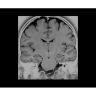

• NeuroWorks — универсальное решение для визуализации анатомии головного мозга, позвоночника, сосудов и периферических нервов с четкой дифференциацией тканей.